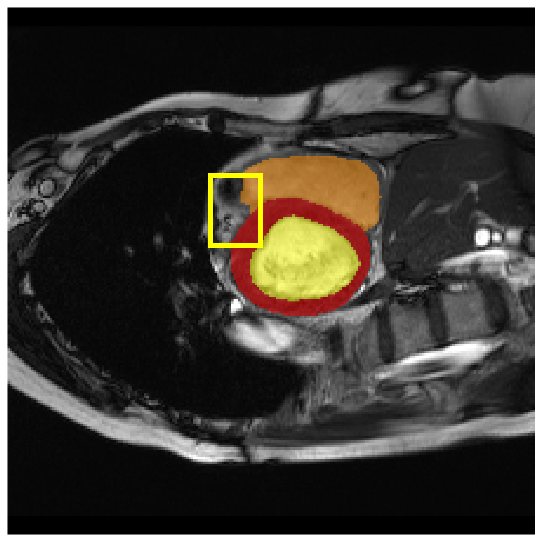

Medical image segmentation plays a critical role in various diagnostic workflows, as it enables accurate delineation of anatomical structures and pathological regions, thereby enhancing disease interpretation, treatment planning, and outcome prediction. Jang et al. [1] has demonstrated that improved segmentation performance can lead directly to reduced diagnostic error rates and increased clinician confidence. Building on the remarkable success of deep learning across diverse domains [2, 3, 4, 5], recent progress in medical image segmentation has been primarily driven by deep learning. Since the introduction of U-Net [6], segmentation methods have rapidly evolved, with convolutional neural networks (CNN)-based models [7, 8, 9] and Transformer-based models [10, 11, 12] showing superior performance in computed tomography (CT) and magnetic resonance imaging (MRI) segmentation. However, various challenges such as blurriness, noise, and low contrast often hinder the accurate diagnosis of diseases. Applying various image enhancement techniques to generate an enhanced image from the input can alleviate this problem, as existing methods have demonstrated improved segmentation accuracy [13, 14, 15]. Nevertheless, input images may unintentionally lose crucial information contained in the original image during enhancement. As a result, the segmentation model suffers from performance degradation (Fig. 1(a) and (b)). Therefore, we argue that it is crucial to leverage the advantages of both the original and enhanced images through image fusion strategies.

4.3.2 Visual Comparisons

Visualization of our method on the Synapse and ACDC datasets is shown in Fig. 3(a) and Fig. 3(b). For the Synapse dataset illustrated in Fig. 3(a), FCT failed to accurately segment SM and GB, while MERIT achieved precise segmentation of SM but struggled with GB. In contrast, our method achieved accurate segmentation of both SM and GB. Regarding the ACDC dataset shown in Fig. 3(b), while previous methods achieve comparable segmentation of the Myo and LV to the GT, they exhibit noticeable errors on the RV, including invasion into adjacent organs and misrecognition. On the other hand, our method accurately segments across all three structures Myo, LV, and RV, performing as precisely as the GT. We demonstrate the superiority of our method quantitatively and qualitatively.